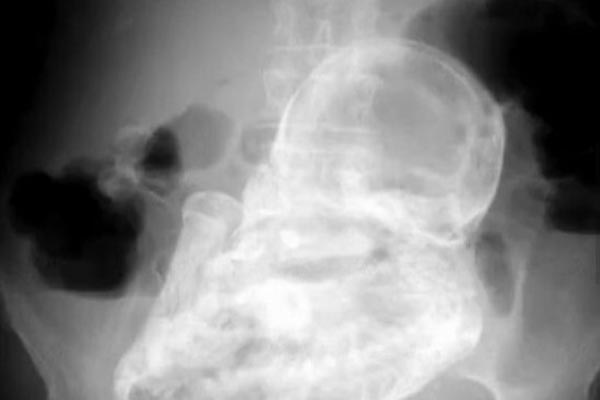

Kada je 82-godišnja žena došla na pregled zbog bolova u trbuhu, liječnici u bolnici u Bogoti otkrili su rijedak slučaj litopediona, odnosno okamenjenog djeteta, javlja AP.

Zbog čega je točno boli trbuh otkriveno je rendgenskim pregledom. ‘Pacijentica je primljena 8. prosinca s dijarejom, a liječnik koji ju je pregledavao otkrio je kod nje nešto neobično te ju je poslao na rendgensko snimanje', rekao je dr. Kemer Ramirez iz bolnice u Bogoti.

Ondje su otkrili da se u njezinom abdomenu nalazi ‘kameno dijete', odnosno fetus koji je preminuo za vrijeme izvanmaternične trudnoće. U slučajevima kada je fetus prevelik da bi ga tijelo razgradilo i apsorbiralo, on se kalcificira, čime se sprječava infekcija.